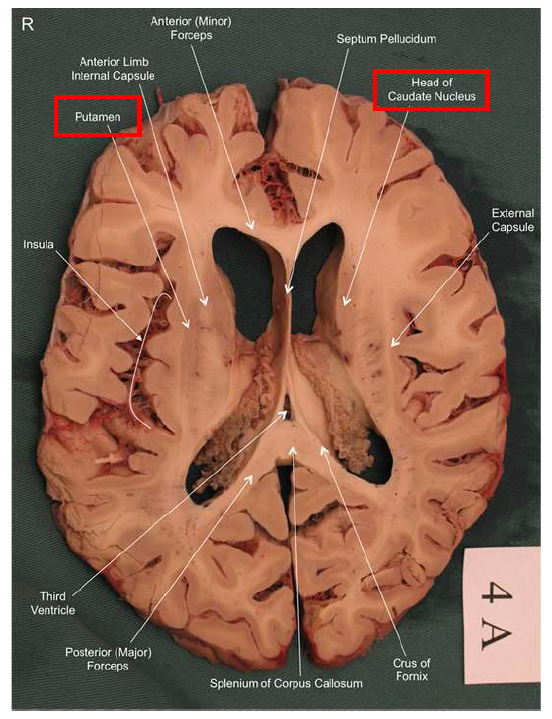

What structure is the major input to the basal ganglia?

striatum

What is the function of the nucleus accumbens (ventral striatum)?

Plays a major role in the brain's reward system, motivating us to seek pleasurable experiences.

Lesion → anhedonia